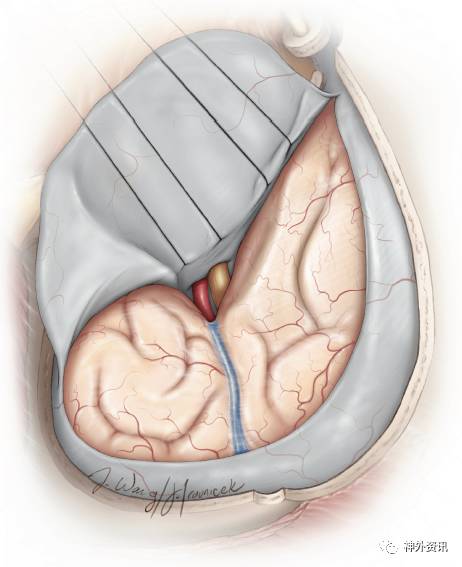

图10:眶颧入路的硬膜内暴露,可见前颅底和中颅底广阔的手术视野(感谢Rhoton教授对图片的授权)。

图39:半圆形切开硬膜,基底指向眶尖。该切口的目的在于暴露颞上回、侧裂和额下回。注意须将额部切口延伸至骨窗拐角处,以便充分利用额下空间。

图40:用数根缝线牵拉硬膜,以利于暴露。缝合点应靠近硬膜辦基底部,而非其边缘,这样可以最大程度地牵开眶内容物、颞肌等软组织,以充分利用硬膜内额下径路。